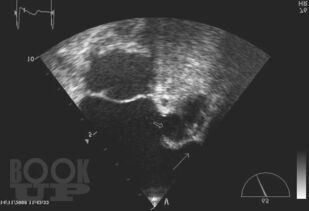

Книга посвящена одной из актуальных проблем кардиологии—тромбоэмболическим осложнениям у больных с аритмиями. Подробно обсуждаются молекулярные и генетические механизмы тромбообразования при аритмиях, клинические и инструментальные признаки внутрисердечных тромбов, а так же способы их визуализации. Приводятся данные о способах оценки риска тромбоэмболических осложнений и тактике антитромботической терапии в различных группах больных с аритмиями. Отдельно освещаются вопросы антитромботической терапии в сложных клинических ситуациях — при хирургических операциях, в случае обострения ИБС, при беременности, при проведении катетерной деструкции. Поводом для выхода второго издания книги послужило появление представителя нового класса антитромботических средств — дабигатрана этексилата, в связи с чем международное кардиологическое сообщество поменяло рекомендации по профилактике тромбоэмболических осложнений у больных с аритмиями. Для кардиологов (в том числе интервенционных), терапевтов, студентов медицинских вузов.